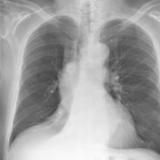

Mass RLL collapse 5 PA

Date: 03/02/2006

Views: 3936